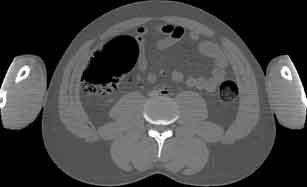

Visible Human male: Sectio transversalis 1685

CT

NMR

Pd                          / T2 \                         T1